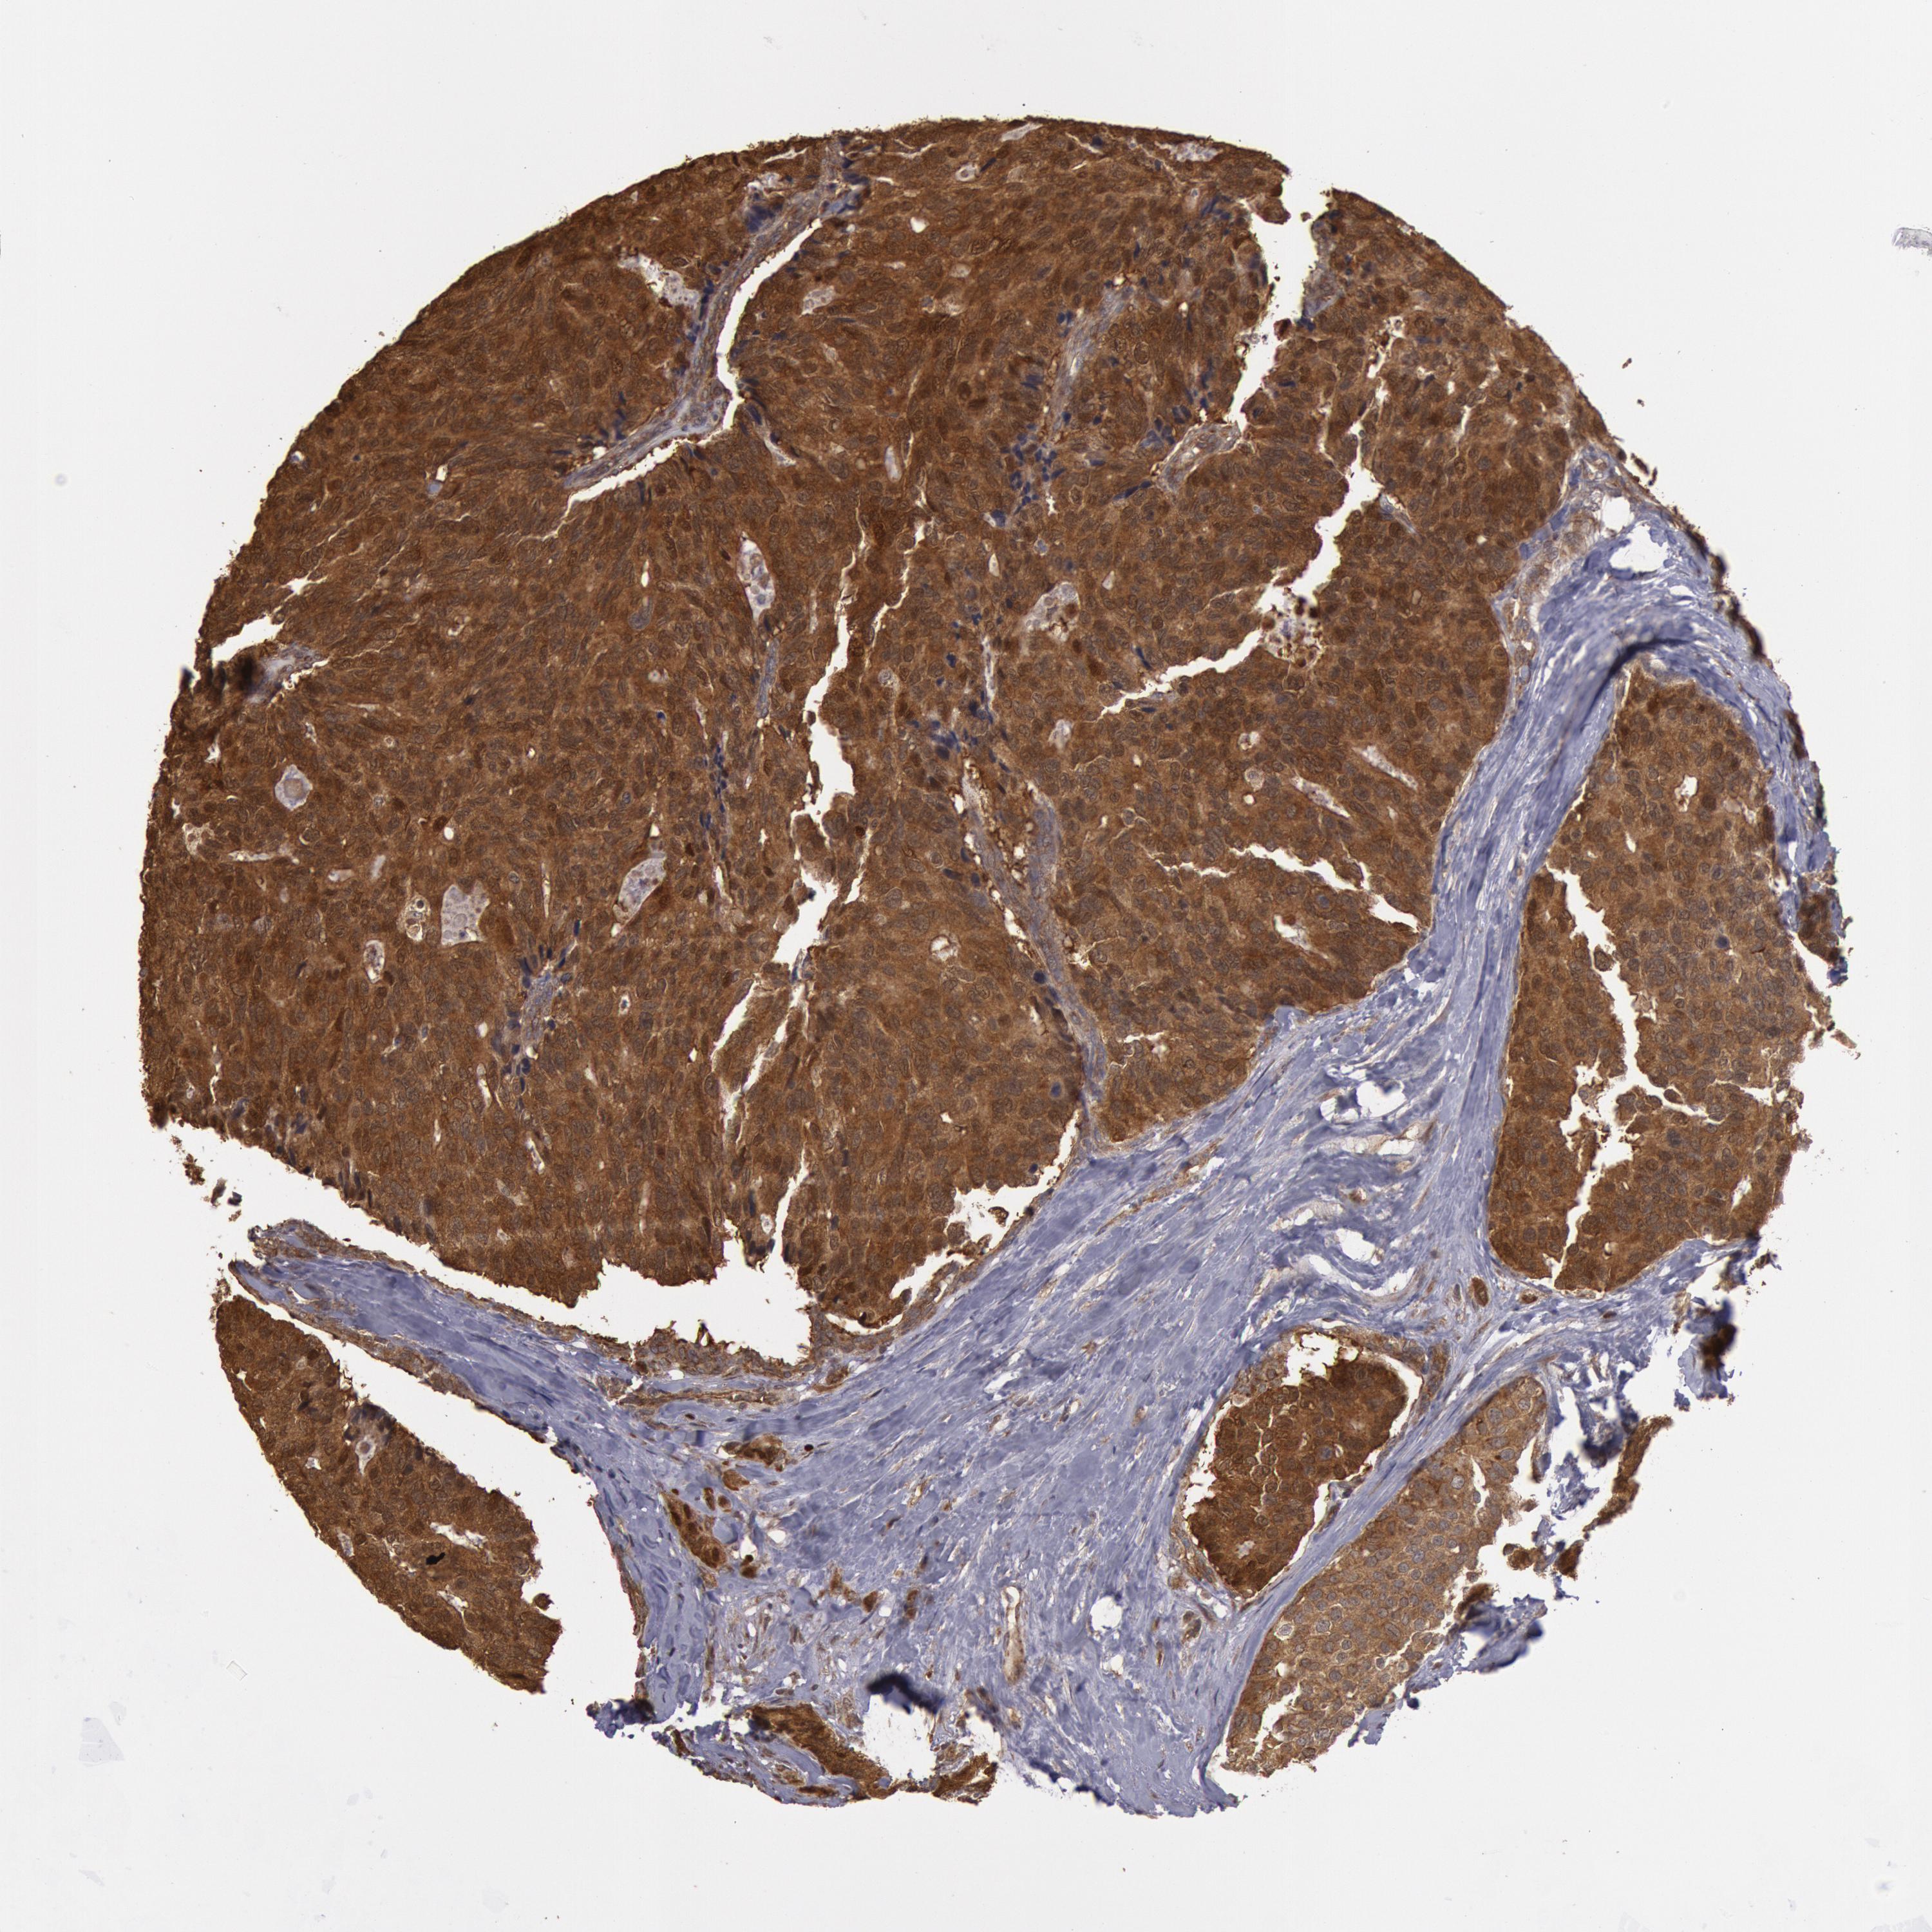

CANCER BREAST CANCER Show tissue menu

BRCA TCGA BRCA VALIDATION PROTEIN EXPRESSION

ANTIBODIES

AND

VALIDATION